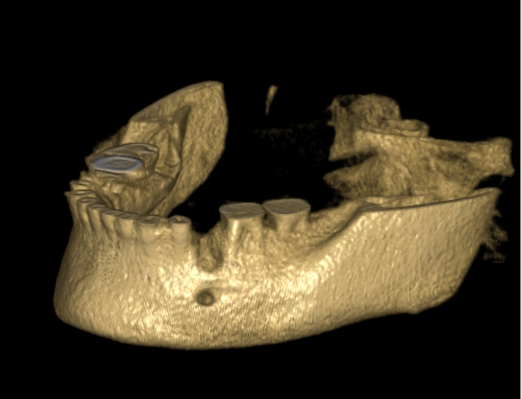

Tyto postupy nám umožní doplnit chybějící množství kosti v čelistech pacienta i zlepšit kvalitu kosti. Většinou se setkáváme s omezenou nabídkou kostní tkáně díky resorpčním (úbytkovým) procesům způsobených věkem či vytržením zubu, přítomností anatomických struktur jako je čelistní dutina, nervový kanál nebo patologických či poúrazových stavů - cysty, zlomeniny.

Při ztrátě molárů a premolárů v horní čelisti a jejich náhradě implantáty se často setkáváme s nedostatečnou

vertikální nabídkou kosti pod čelistní dutinou, často doprovázenou i nedostatečnou horizontální nabídkou a sníženou kvalitou kosti (v oblasti 2. premoláru v 50%, v oblasti moláru až v 80% případů nedostatečná kostní nabídka)